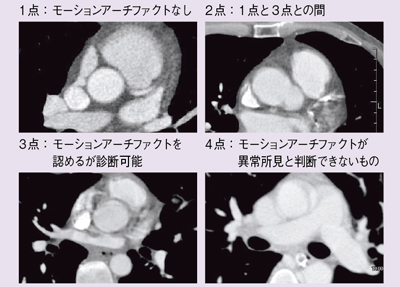

モーションアーチファクトの軽減効果について,2010年4月〜2011年5月に当センターに入院した患者47例にFlash Spiralで胸部造影CTを施行した(Group F)。内訳は,外因性症例14例,内因性症例33例であった。比較対象は2009年4〜12月に従来の64MDCTで検査した53例(Group C)で,内訳は外因性症例が20例,内因性症例が33例であった。評価方法は図5のとおりである(2002年にRadiology掲載のRoosらの評価点数使用)。評価部位は,上行大動脈,大動脈弓部,下行大動脈,大動脈分岐部,左冠動脈主幹部,右肺動脈の6部位とした。読影は,病歴を知らない放射線科医が行った。本検討の目的は,病変の有無ではなく,画像が診断に耐えうるかどうかであり,解析にはMann-Whitney U検定を用いた。

図5 モーションアーチファクト軽減効果の評価方法

結果は,Group CはGroup Fに比べて,どの評価部位においてもモーションアーチファクトが多い傾向が認められた。特に,心臓に近い上行大動脈,左冠動脈主幹部では,モーションアーチファクトと病変の診断がつかない「4点」と評価される症例が多く見られた。一方,Group Fでは,全評価部位の中で左冠動脈主幹部に2例のみ,「4点」の症例を認めた。

次に,上行大動脈における心拍数と画質との関係を評価した。結果は,Group Cでは心拍数80bpm以上の症例で25%が「4点」であった。一方,Group Fでは心拍数にかかわらず,「4点」の症例は1例もなく,全体としては「1点」と「2点」に評価される傾向が認められた。

左冠動脈主幹部についても同様に評価した結果,Group Cでは全体の46%が「4点」であり,心拍数80bpm以下の症例についても,そのうちの33%が「4点」であった。さらに,80bpm以上の症例に至っては,52%が「4点」であった。一方,Group Fでは,「4点」がついたのは心拍数100bpm以上の2例のみであった。つまり,Flash Spiralで撮影した場合には,心電図同期を行わないにもかかわらず,高い精度で左冠動脈主幹部の病変とモーションアーチファクトの鑑別が可能であると言える。